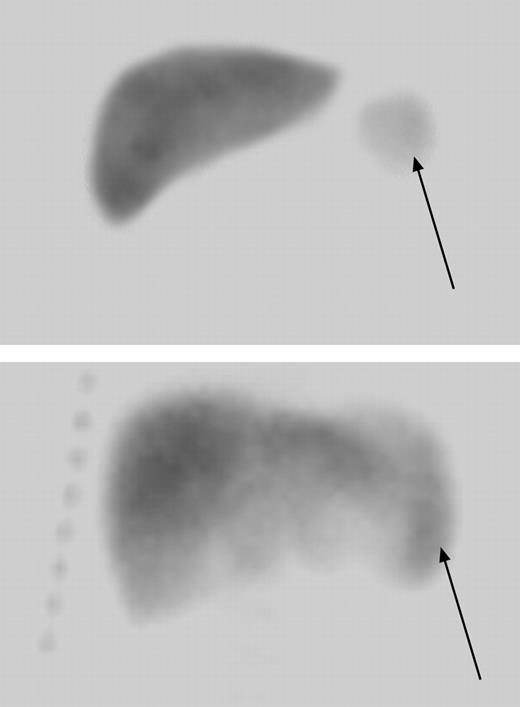

Four patients had undergone surgical splenectomy before enrollment in the original HUSOFT study. There were 17 usplenectomized children enrolled in the extension study, 14 of whom had spleen function assessed at baseline, year 2, and year 4. After 4 years of hydroxyurea therapy, 3 of the 14 (21.5%) children had normal splenic uptake, 3 (21.5%) had decreased uptake, and 2 (14%) had markedly decreased uptake. Only 6 (43%) patients were functionally asplenic (absent uptake) upon study completion, in contrast to the expected 94% incidence of asplenia among untreated age-matched children with SCA based on red-cell pit counts (P < .001).27 Remarkably, one infant with markedly decreased and another with absent splenic uptake prior to hydroxyurea treatment regained normal splenic uptake after 4 years of hydroxyurea therapy (Figure 2). Neither of these 2 patients received erythrocyte transfusions during the extension study.

Radionuclide liver-spleen scan showing normalization of splenic uptake after extended hydroxyurea therapy. A 7-month-old child with markedly decreased splenic uptake at baseline (arrow in top panel) regained splenic uptake after 4 years of hydroxyurea therapy (bottom panel). The arrow in the lower panel denotes the location of splenic uptake and indicates a slightly enlarged spleen measuring 9.3 cm in length.

Possible delay in the progression toward functional asplenia and actual recovery of splenic function in 2 cases were observed during the hydroxyurea extension study. This observation, coupled with the lower proportion of asplenic patients after 4 years of hydroxyurea therapy (43% versus the expected 94%), suggests that hydroxyurea therapy can prevent loss of spleen function or even restore it as reported in older patients.21,22,39 However, the maintenance or recovery of splenic function raises the possibility that these children will be at prolonged risk for acute splenic sequestration. While prospective comparison with untreated patients remains necessary to define if such a risk exists, the management of acute and chronic splenomegaly could emerge as a treatment-associated problem for children with SCA receiving hydroxyurea therapy. Children with prolonged and significant splenomegaly may not tolerate full-dose hydroxyurea therapy14 and may be at long-term risk for acute splenic sequestration. Partial splenectomy could become a therapeutic option for these children, because it offers the advantage of preserving some immune function while controlling acute symptoms of splenomegaly.40,41